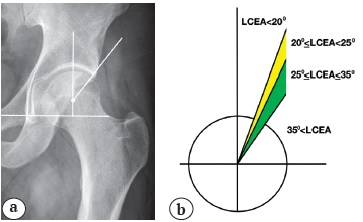

Рентгенологическая диагностика патологии вертлужной впадины. Наиболее важными критериями оценки анатомии вертлужной впадины являются центрально-краевой угол, предложенный Wiberg в 1939 г. и модифицированный S. Ogata в 1990 г., передний центрально-краевой угол (угол Lequesne) и угол наклона крыши вертлужной впадины (угол Tönnis).

Для определения истинного значения латерального покрытия головки бедренной кости рассчитывается латеральный центрально-краевой угол Wiberg (LCEA) в модификации S. Ogata [32]. Для построения этого угла на обзорной рентгенограмме таза проводят прямую линию, проходящую через основания «фигур слезы». Вторую линию проводят через центр головки бедренной кости, перпендикулярно первой линии. Третья линия проходит от центра головки по латеральному краю склерозированной части суставной поверхности. Угол Wiberg, образованный второй и третьей линиями — острый угол, который в норме составляет от 25° до 35° (рис. 1). Избыточный угол более 35° свидетельствует о pincer-деформации вертлужной впадины и может быть причиной импинджмента. Вариантом строения вертлужной впадины с избыточным покрытием являются глубокая вертлужная впадина и протрузия. Данный тип строения вертлужной впадины не является противопоказанием, но не благоприятен для выполнения артроскопии, с точки зрения технических сложностей и исхода [33]. Промежуточное значение от 20° до 25° считается пограничной дисплазией, а величина менее 20° — уже показатель дисплазии.

Рис. 1. Определение латерального центрально-краевого угла (LCEA) (показан левый тазобедренный сустав):

a — определение угла Wiberg в модификации Ogata;

b — варианты строения вертлужной впадины в зависимости от угла LCEA

Fig. 1. Determination of the lateral center-edge angle (LCEA) (left hip joint):

a — determination of Wiberg angle in Ogata modification;

b — variants of acetabulum structure depending on the LCEA

Многочисленные исследования показали хорошие результаты артроскопии у пациентов с ФАИ на фоне пограничной дисплазии вертлужной впадины при условии шва суставной губы и восстановления целостности капсулы сустава [34]. Но стоит помнить, что каждый миллиметр резекции края вертлужной впадины при восстановлении суставной губы уменьшает величину угла LCEA примерно на 1° [35]. При выявлении у пациента истинной дисплазии стоит отдавать предпочтение выполнению периацетабулярной остеотомии, возможно, с одновременной артроскопической коррекцией внутрисуставных повреждений и деформаций [36].